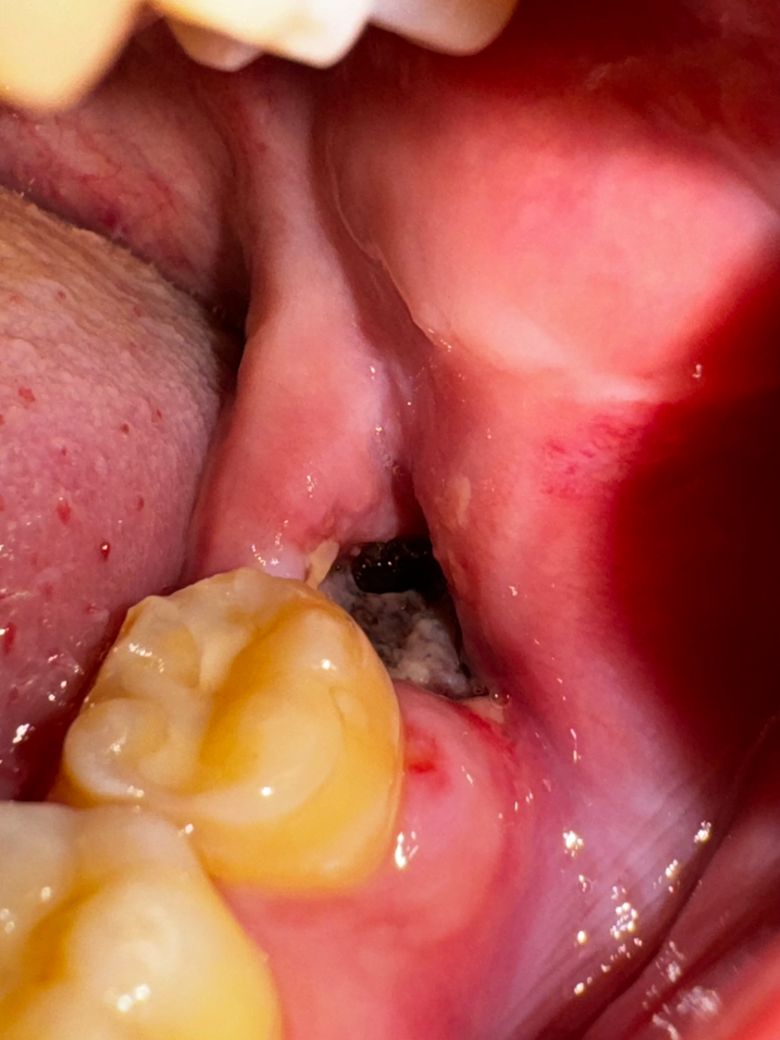

이거 혹시 드라이소켓인지 알 수 있을까요?

사랑니 발치 후 6일 째입니다. 원래 회색처럼 보이는 막(혈병?)이 구멍 전체를 메우고 있었는데, 어느날 갑자기 회색 부분이 일부 사라지고 구멍이 뚫린 것처럼 보이게 되었어요.. 냄새나 통증은 없는데 뭔가 혈병이 떨어졌으니 드라이소켓이 발생한 게 아닌가 걱정되네요..

• 1번 째 사진

드라이 소켓은 감염의 일종으로 통증이 심하고 냄새가 심하게 납니다 .드라이 소켓은 아닌거 같습니다.

정상적으로 아물고 있습니다. 잇몸이 아물면서 짜불아 들게 되면 구멍이 생기게 됩니다. 시간이 지나면 점점 차올라옵니다.

냄새나 통증이 없다면 드라이 소켓을 의심하지는 않습니다. 염증 소견 등은 사진상 보이지 않습니다.

혈병이 떨어졌다고 무조건 드라이 소켓이 생기는 것은 아닙니다.

냄새가 나지 않거나 통증이 없다면 드라이 소켓이 아닐 가능성이 높습니다.